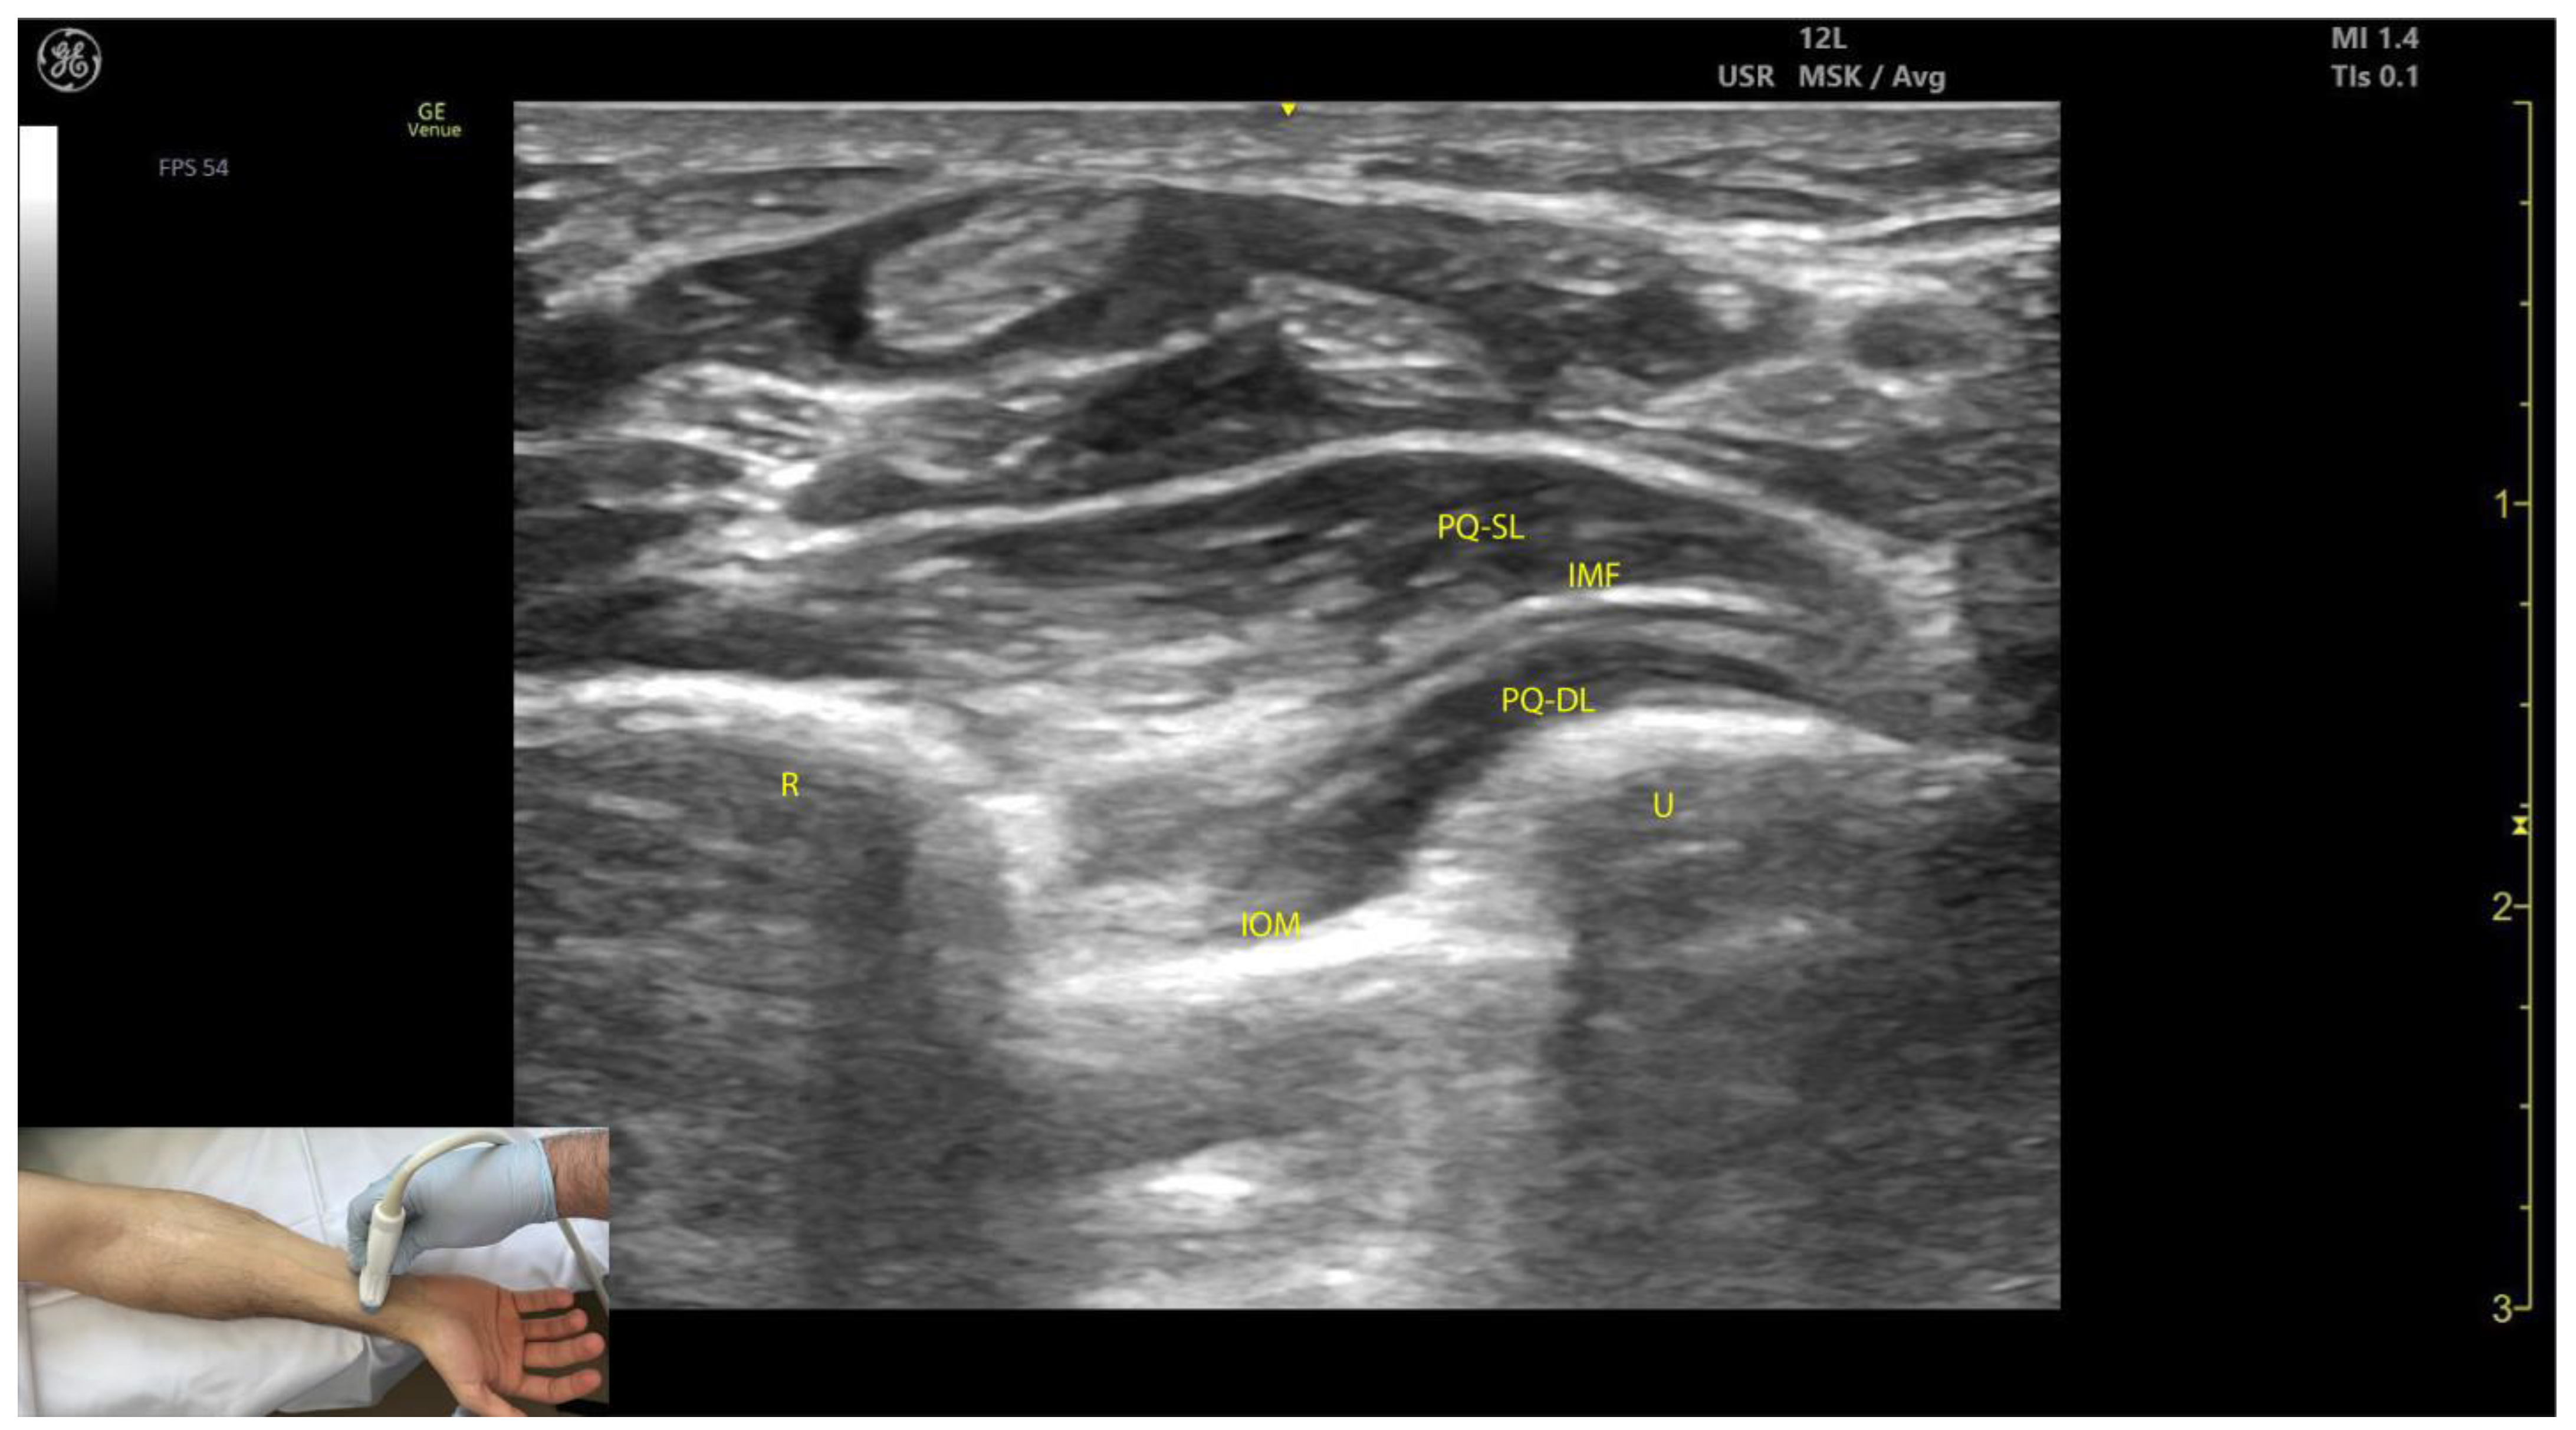

2.7.3. Key Ultrasound Landmarks (Figure 7)

- Muscle position: The PQ is the deepest muscle on the anterior forearm [31];

- Quadrilateral shape: It has a distinct, rectangular shape with parallel muscle fibers [41];

- Unique fiber orientation: The PQ is the only forearm muscle with fibers oriented perpendicularly to the limb, unlike all other forearm muscles, which run longitudinally;

- Two heads: The PQ has superficial and deep heads, separated by an intramuscular fascia that connects the convex surfaces of the radius and ulna [41];

- Deep to the PQ: There is the interosseous membrane and the extensor compartment of the distal forearm [42];

- Superficial to the PQ: There is the FDP, FDS, and FPL tendons, the median nerve, and, if present, the palmaris longus tendon [42];

- External fascia: The PQ muscle is characterized by a well-defined fascia that clearly separates it from adjacent muscle masses, facilitating precise localization during BoNT-A injections.

- Dynamic evaluation: When scanning distally toward the radioulnar joint, the PQ muscle enlarges, while the FDP, FPL, and FDS progressively decrease in size and transition into tendons [43].

2.7.4. Clinical Implications and Injection Strategy

- According to Choung et al., the optimal injection site for the PQ, containing the highest concentration of motor points, is approximately 3 cm proximal to the ulnar styloid [46].

- In our clinical practice, the BoNT-A injections are performed at the point of maximum muscle thickness, as determined by ultrasound. The PQ can be injected either through the volar aspect of the forearm, avoiding the median nerve, or through the dorsal aspect via the extensor compartment and interosseous membrane. Both approaches require ultrasound guidance to ensure accurate delivery while avoiding neurovascular structures and minimizing the risk of complications.